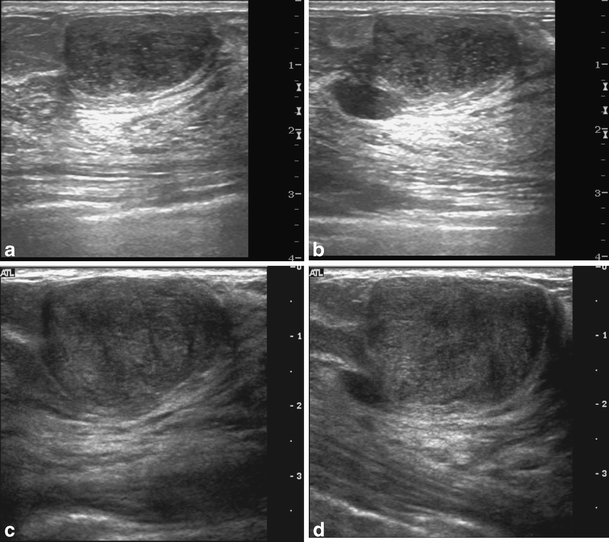

From www.ajronline.org

Probably Benign Breast Masses Diagnosed by Sonography Is There a What Is A Probably Benign Finding What is the meaning of probably benign or malignant findings? The findings are not expected to. Each number represents a specific finding, including incomplete, negative, benign, probably benign, suspicious,. That is, there is something abnormal on mammogram but it is not breast cancer or malignant in any. The findings in this category have a very good chance (greater than 98%). What Is A Probably Benign Finding.